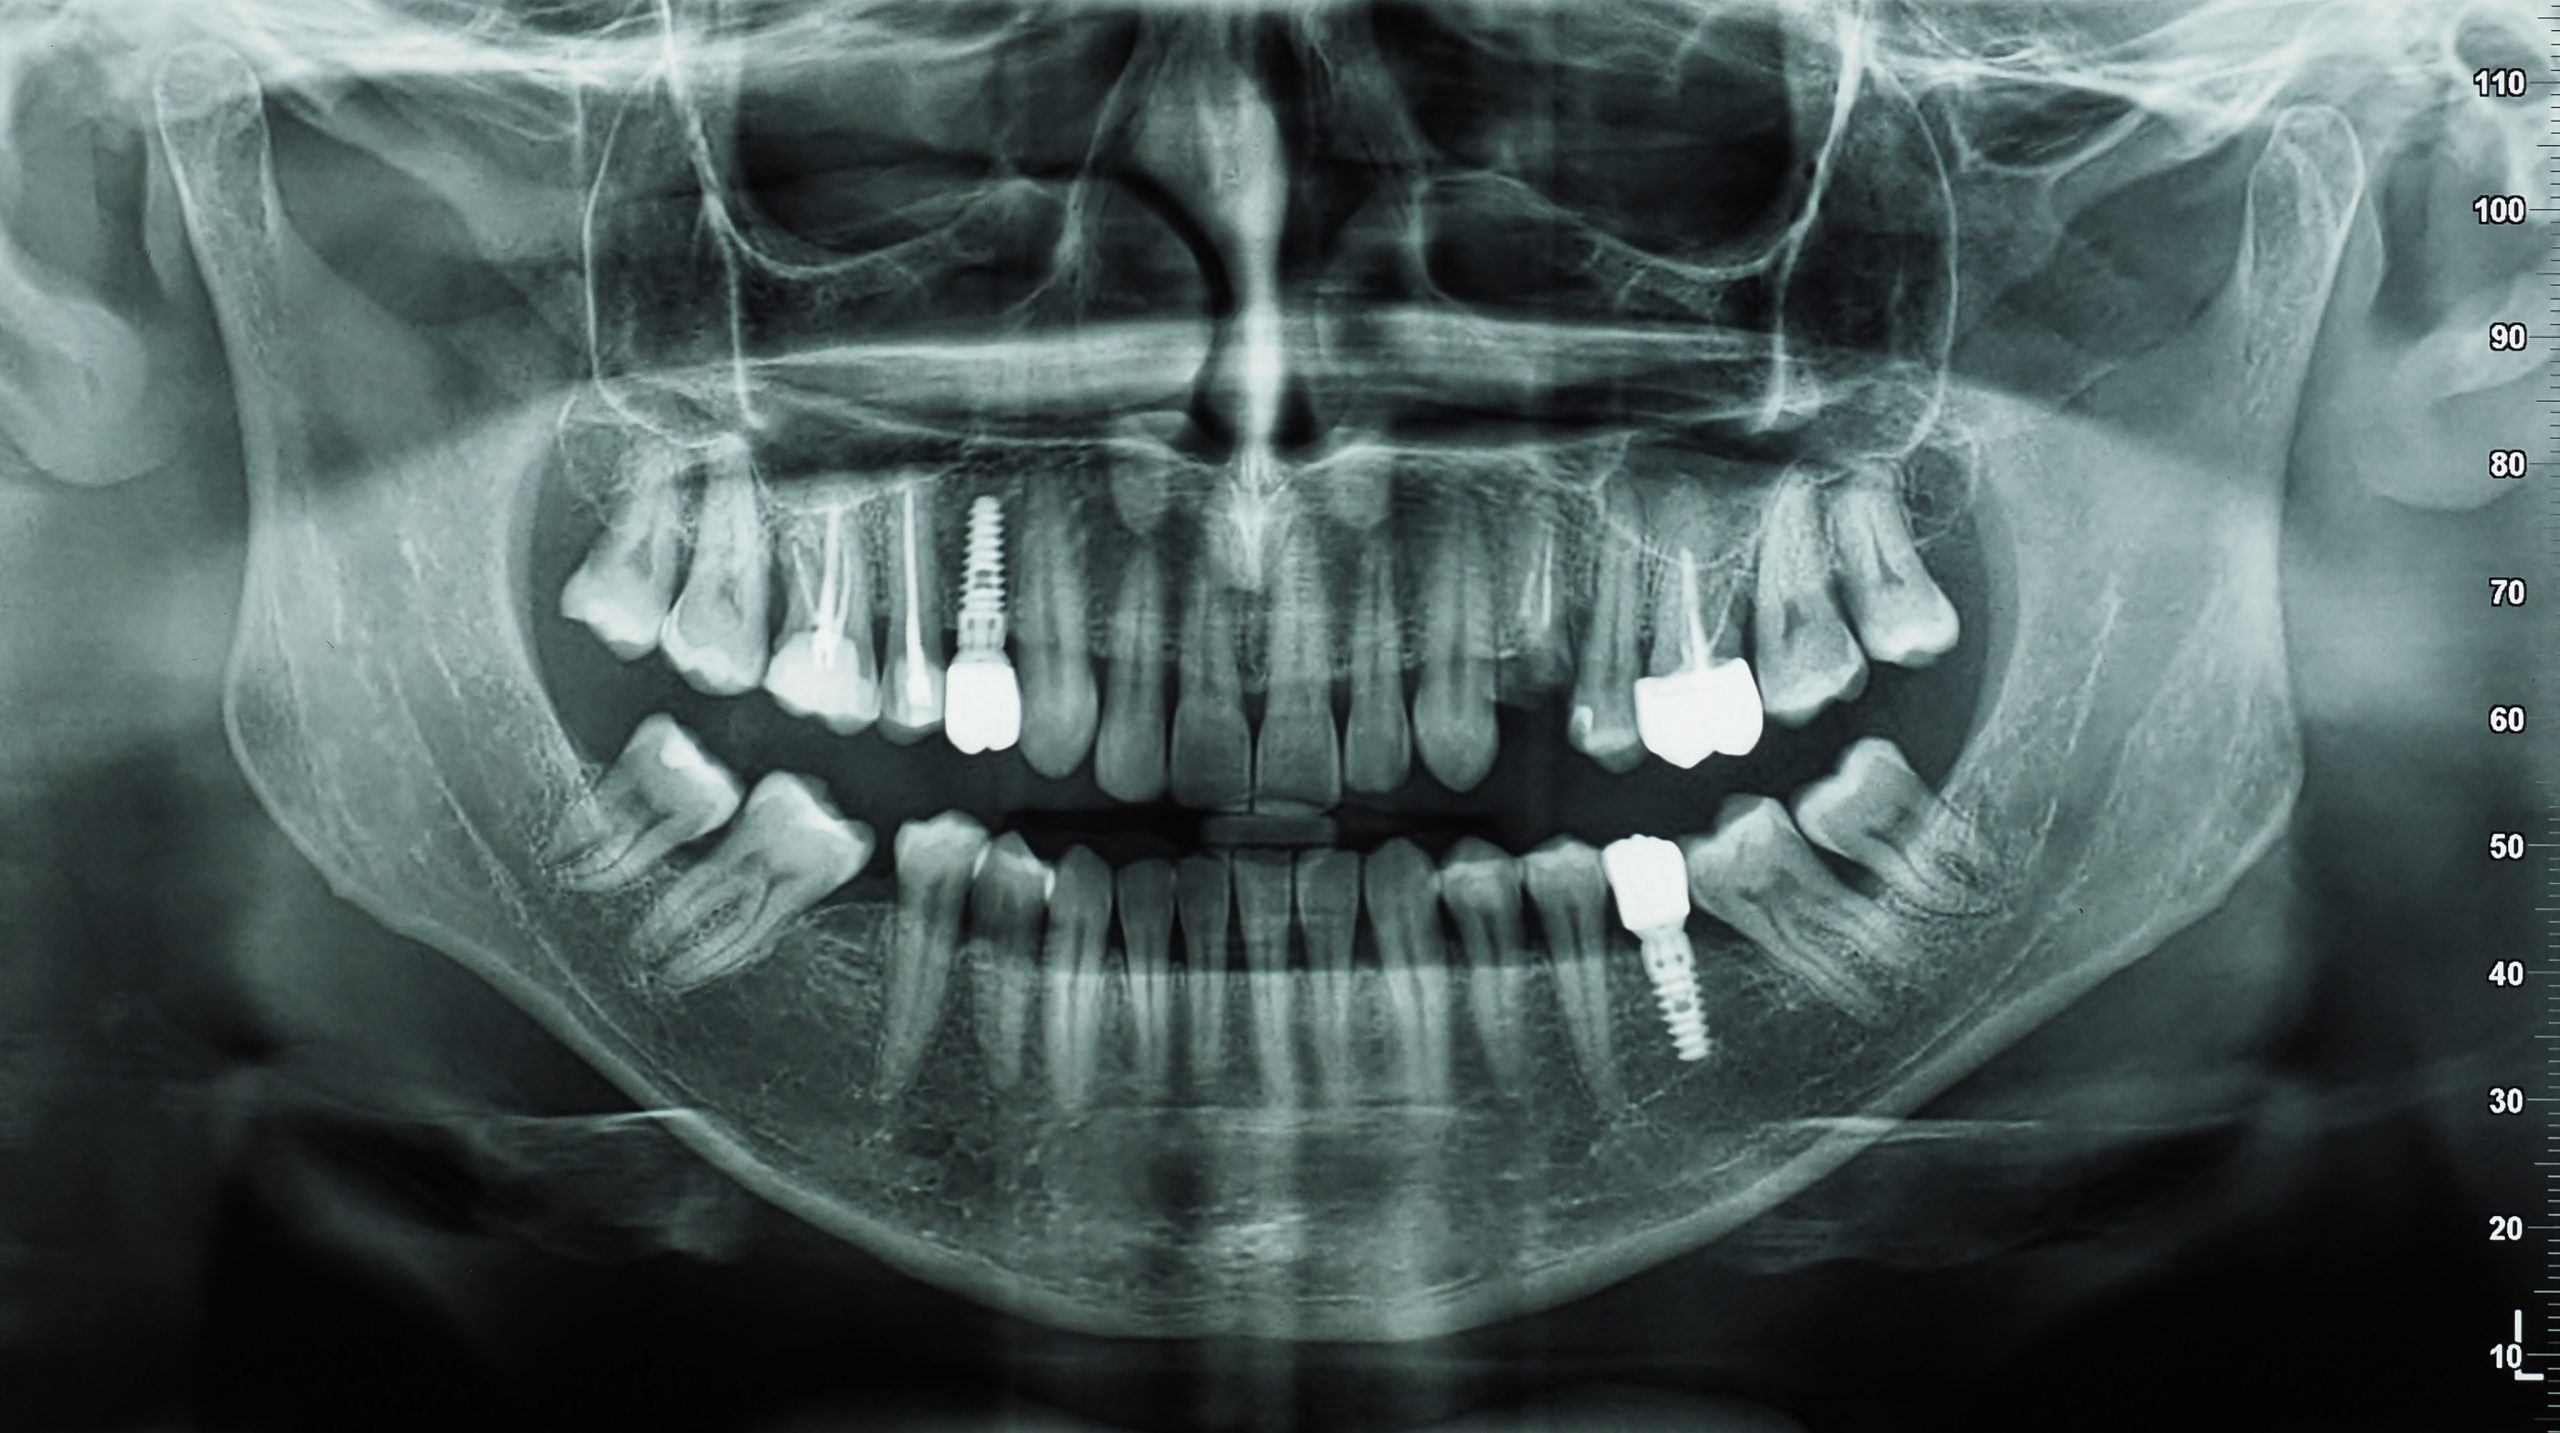

RADIOGRAPHIES

Aujourd’hui, la radiographie dentaire est devenue un instrument indispensable pour suivre la santé bucco-dentaire d’un patient. Elle permet de suivre l’évolution de la structure dentaire et d’anticiper les problèmes (malformations, infections, pathologies, etc.). Grâce à une simple radio des dents, un dentiste peut détecter les anomalies à temps et proposer les soins adéquats.